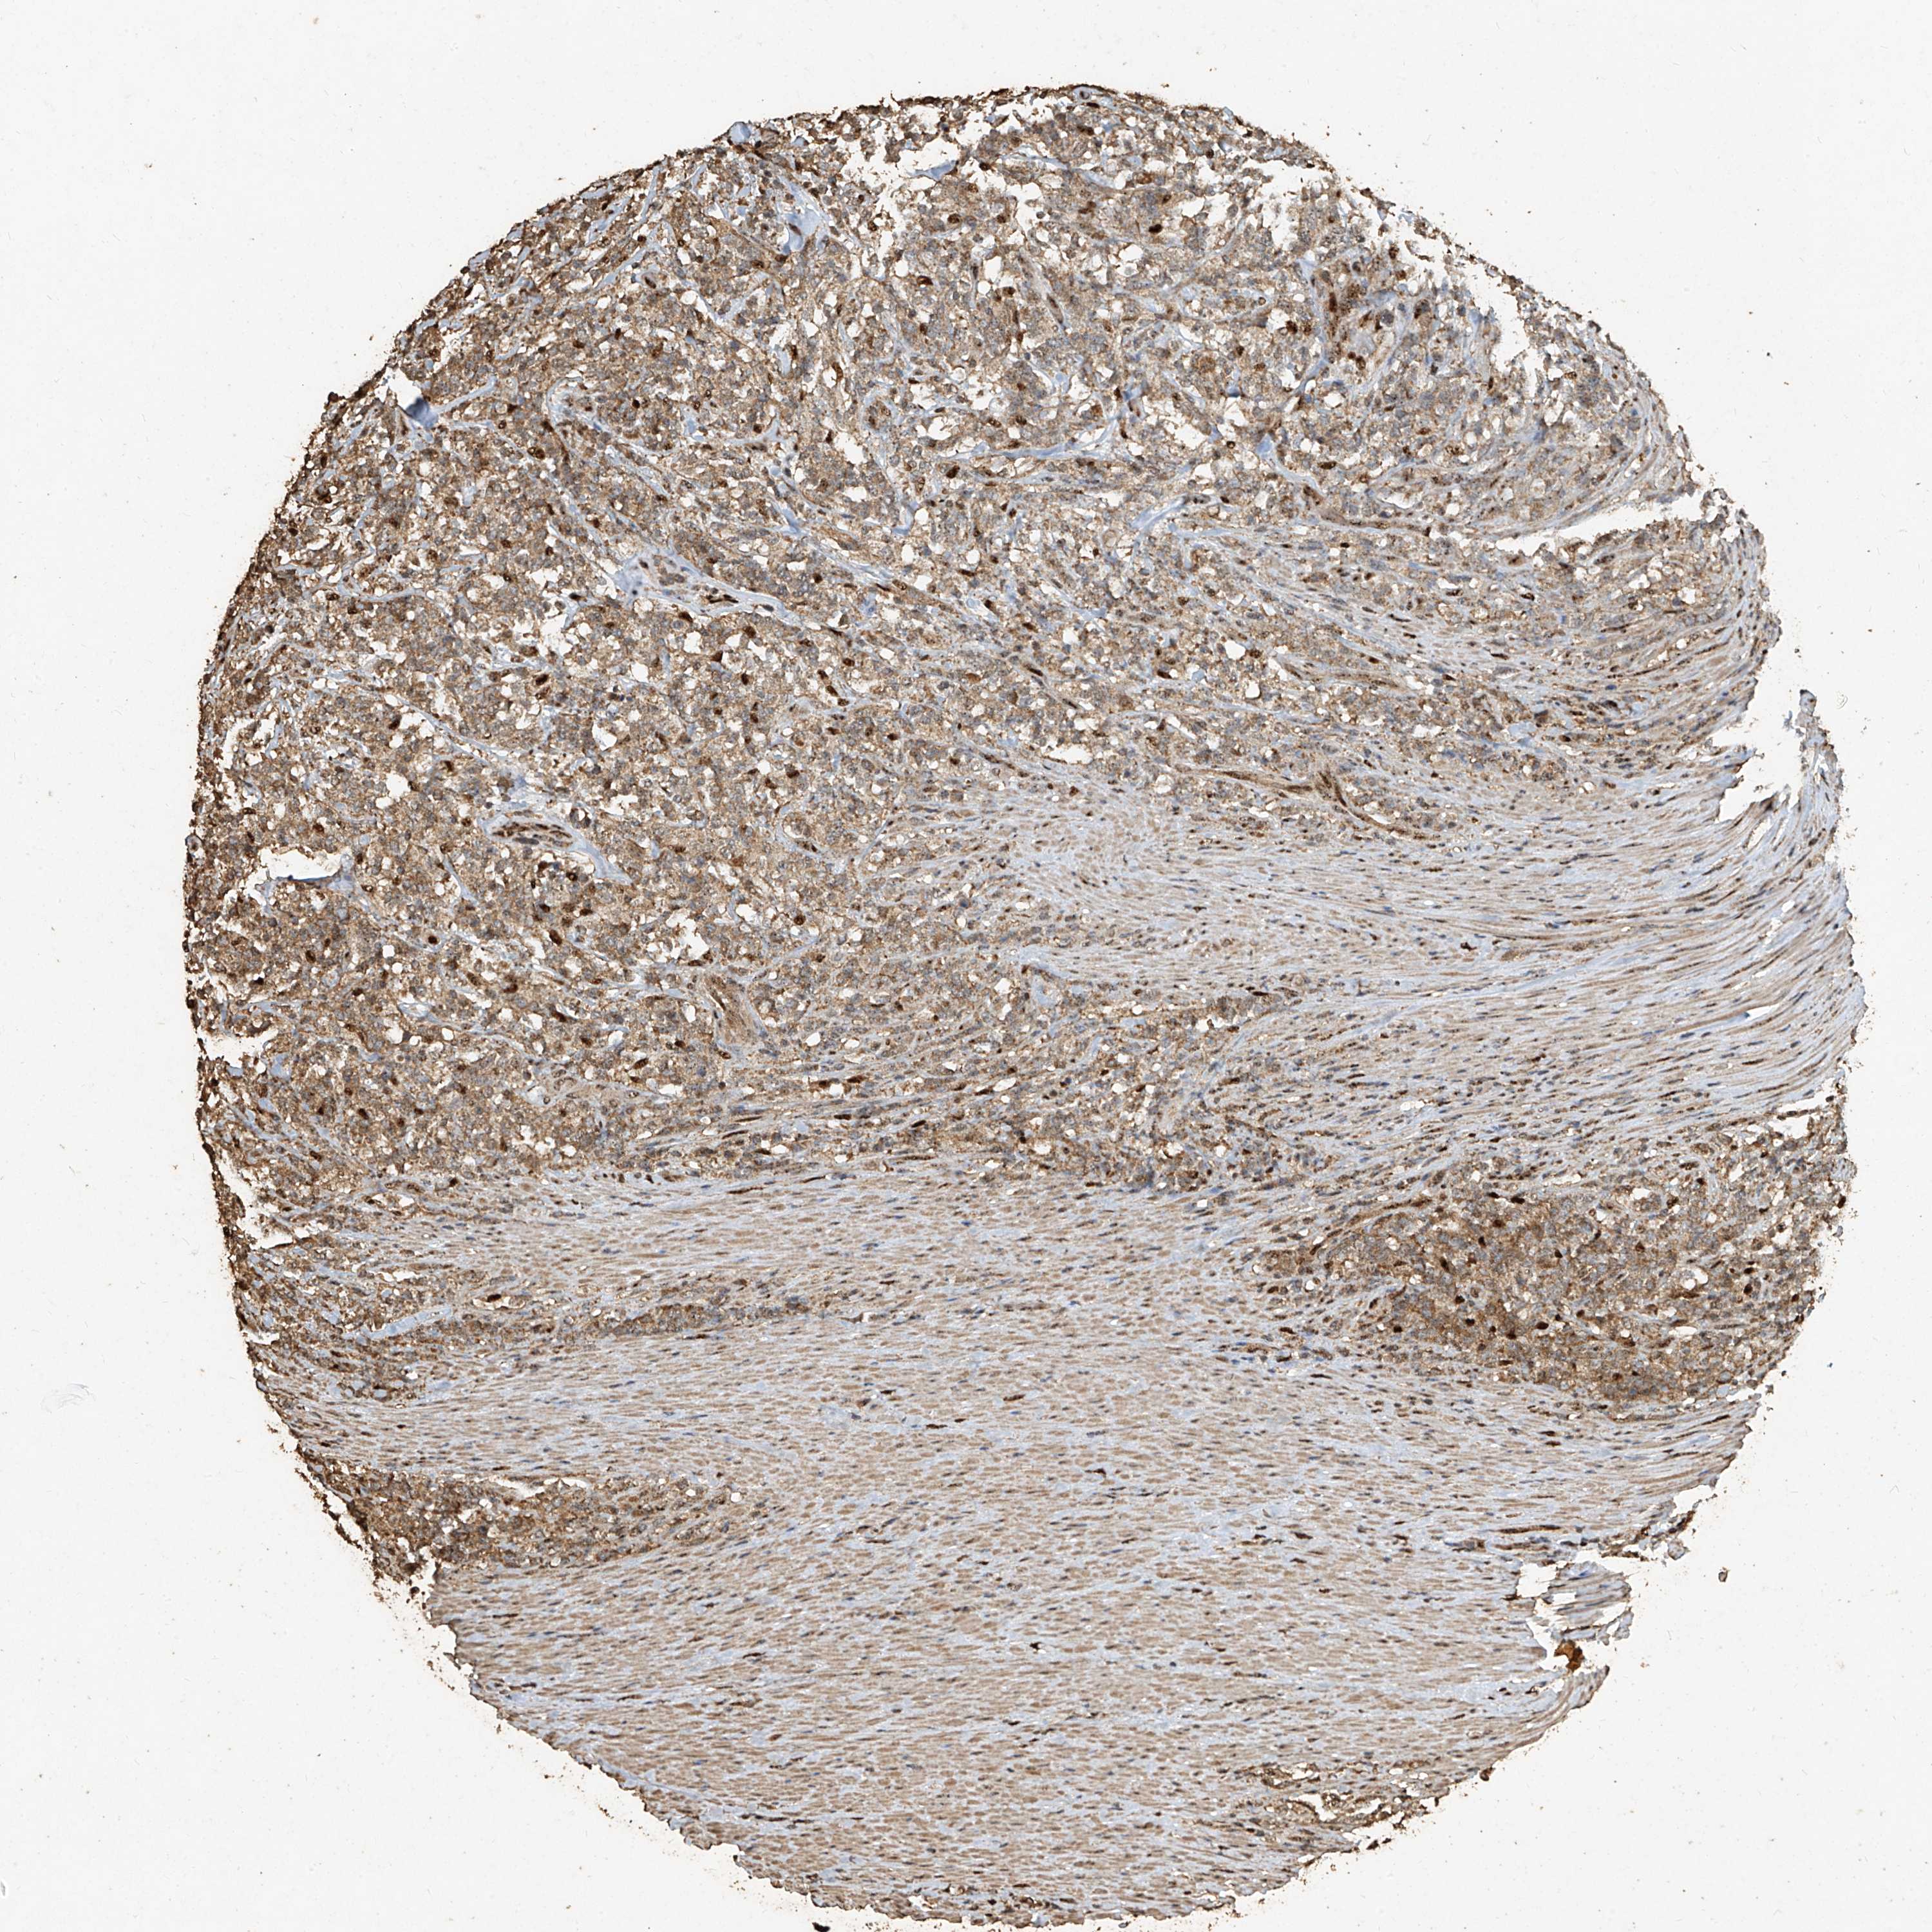

CANCER LYMPHOMA Show tissue menu

LYMPHOMA - Protein expressioni

A mouse-over function shows sample information and annotation data. Click on an image to view it in a full screen mode. Samples can be filtered based on level of antibody staining by selecting one or several of the following categories: high, medium, low and not detected. The assay and annotation is described here.

Each image is clickable and will lead to virtual microscopy that enables deeper exploration of all samples and also displays staining intensity scores, fraction scores and subcellular localization as well as patient and tissue information for each sample.

Antibody HPA045396

Antibody HPA070524

Antibody CAB025331

Staining

High

Medium

Low

Not detected

Intensity

Strong

Moderate

Weak

Negative

Quantity

>75%

75%-25%

<25%

None

Location

Nuclear

Cytoplasmic/membranous

Cytoplasmic/membranous,nuclear

Hodgkin's disease, NOS

Malignant lymphoma, non-Hodgkin's type, High grade

Malignant lymphoma, non-Hodgkin's type, Low grade